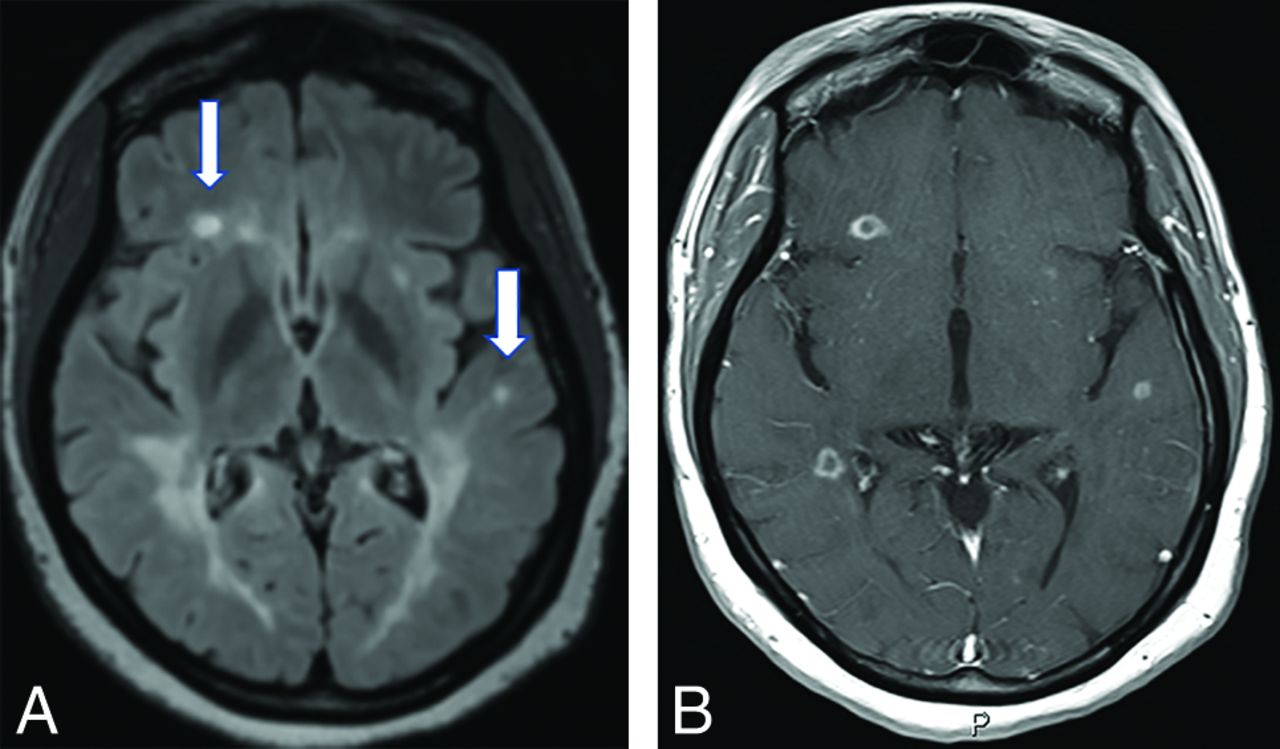

In the article of Okuda et al9 on RIS, 10 of 41 (24%) patients with periventricular, juxtacortical, spinal, or infratentorial white matter lesions had ≥1 enhancing plaque at the time of RIS presentation. Of these 41 patients, MR imaging progression (the presence of new T2 foci, new gadolinium enhancement, or enlargement of pre-existing lesions) on longitudinal MR imaging, fulfilling the DIT criteria, was identified in 59% of the cohort (24/41). In a subsequent multicenter cohort of 456 patients with RIS, the frequency of periventricular, juxtacortical, spinal cord, and infratentorial lesions was 98.7%, 90.1%, 35.2%, and 30.4%, respectively.12 Gadolinium-enhancing lesions were found in 82.3% of this study cohort (Fig 2).12 In a study of 19 patients with RIS and 20 individuals with relapsing-remitting MS (RRMS), no significant difference was found between the groups in T1-weighted and T2-weighted lesion volume or frequency and distribution of lesions.13 In addition to white matter lesions, cortical lesions have been described in 40% of patients with RIS in a study by Giorgio et al.14 The authors found that these cortical lesions involved the frontotemporal lobes most commonly and were more frequent in patients with RIS with the following: 1) oligoclonal bands in the CSF, 2) DIT on follow-up, and 3) coexistent cervical cord lesions. The unanswered question remains as to whether patients with RIS with cortical lesions have a higher MS conversion rate.

A, A 32-year-old woman being evaluated for benign positional vertigo. The FLAIR scans have severe confluent periventricular disease and a few juxtacortical foci (arrows) of high signal. B, On postgadolinium scanning, numerous ring-enhancing demyelinating lesions are present, both periventricular-periatrial on the right and juxtacortical bilaterally.